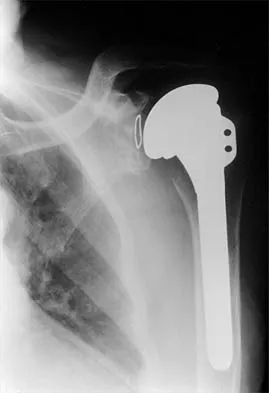

A 70-year-old man who underwent an uncomplicated large rotator cuff repair 6 months ago is now seeking a second opinion regarding persistent pain and weakness in his shoulder. Examination reveals that his incision is well healed and unreactive. The surgical report suggests that the tendons were secured back to bone with sutures through the greater tuberosity. Figure 28 shows a radiograph that was obtained 1 week ago. What is the most likely diagnosis?

Explanation

Symptoms can persist following a rotator cuff repair for a variety of reasons. In the early postoperative period, infection is the primary concern. Stiffness and loss of motion can occur because of postoperative scarring. Complex regional pain syndrome can occur but is rare, and the diagnosis is not made with a plain radiograph. This radiograph shows a superiorly migrated humeral head that articulates with the acromion, indicating that the repair has failed. While large to massive tears may fail more commonly than once thought, the clinical outcome may be satisfactory in many patients. Mansat P, Cofield RH, Kersten TE, Rowland CM: Complications of rotator cuff repair. Orthop Clin North Am 1997;28:205-213.